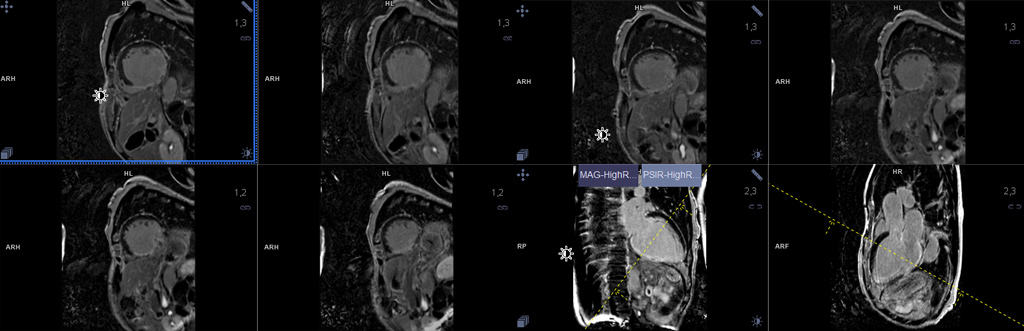

It is an advanced technology for creating images by electromagnetic fields to evaluate the structure and function of the cardiac. Also, highly significant in the evaluation of the clinical coronary blood flow, as well as precisely evidence that benefits the classification of cardiovascular disease and the therapy strategies for the patient as an individual suitably.

The strength of cardiac MRI is the high resolution of the cardiac images with elevated efficiency in the investigating process thorough blood flow through all cardiac compartments. Besides, the recipients do not experience discomfort, and hospitalization is unnecessary with this method.